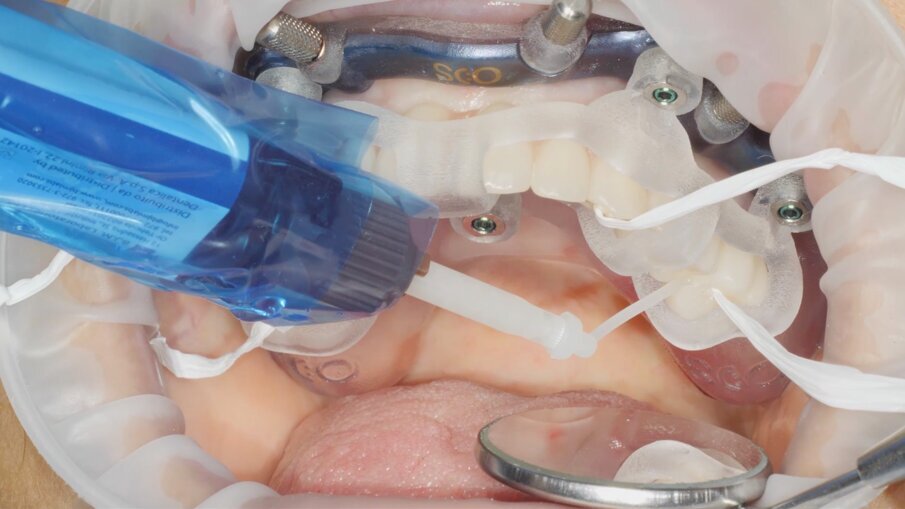

Veniamo quindi al posizionamento della protesi mediante carrier, a sua volta ancorato agli stessi punti di fissaggio della dima base. È significativo osservare come la stabilizzazione della sola vite palatale consenta l’allineamento perfetto tra i sistemi di fissaggio (Fig. 22), mentre il dettaglio mostrato in Fig. 24 illustra efficacemente come prima della cementazione della protesi l’accoppiamento e la centratura del foro protesico appaiano perfetti, confermando quindi come l’obiettivo di alloggiamento della protesi nella sede prestabilita sia stato colto. Per la fase di cementazione con cemento duale si è prestata attenzione alla realizzazione di un foro aggiuntivo per permettere al materiale di raggiungere gli abutment. I fori di accesso alle viti vengono tappati con filo di teflon (Figg. 25, 26) ed è a questo punto possibile andare a fissare la protesi e rimuovere il sistema carrier (Fig. 27). Lasciamo la dima in posizione, così che nell’eventualità in cui un abutment non dovesse essere stato cementato correttamente, ci riserviamo la possibilità di riprendere il posizionamento strategico dell’intero sistema Pcube, intercettando possibili impedimenti alle manovre di finalizzazione del caso.